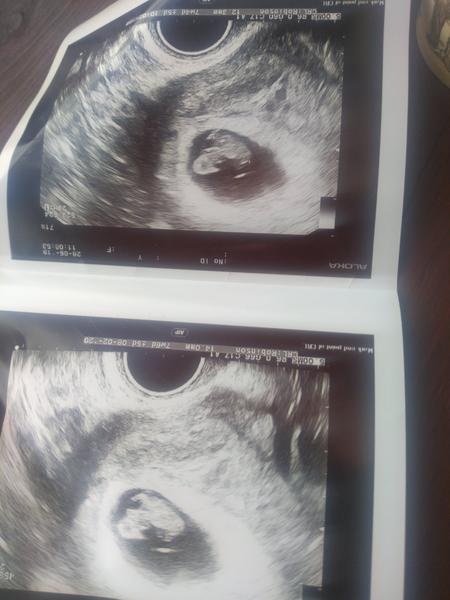

@elzab tak tady ti predstavuji nase malinke embrijko <3 jedenapul centaku velkej chlapak 😀 (možná 2) uvidíme za 14dnu a na screaningu. Jelikož mam dve dioptrie a tvrdim ze bryle nepotrebuju, tak jsem na obrazovce videla jen cosi a žádné srdíčko 😀 ale vse je.